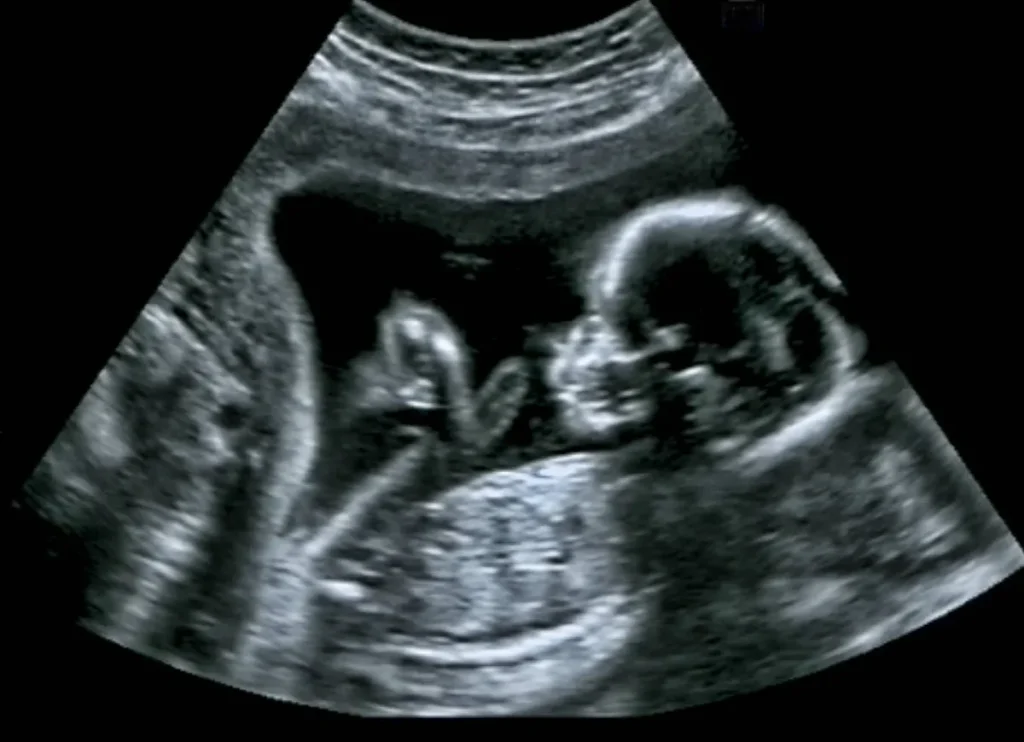

وشاركت في التجربة نحو 60 امرأة حاملاً في الأسبوع الـ35 من الحمل، وجرى تعريض 39 منهنّ لتسجيلات صوتية لقصص باللغة الفرنسية، وهي اللغة الأم الخاصة بهن، لمدة 10 دقائق، ثم استمعن إلى تسجيلات للقصص عينها باللغتين الألمانية والعبرية لـ10 دقائق أيضاً، مع تكرار هذه العملية بشكل يومي طوال مرحلة الحمل.

ويوضح اختصاصي علم النفس العصبي السريري بجامعة مونتريال، الباحث أندريان رينيه، أنّ اختيار اللغتين الألمانية والعبرية يعود إلى الاختلاف الكبير بينهما وبين اللغة الفرنسية من ناحية الصوتيات، وخواص النطق. أما باقي الحوامل المُشاركات في التجربة، وعددهن 21 امرأة ضمن مجموعة التحكّم، فلم يتعرَّضن لأي مؤثرات خارجية خاصة، وبالتالي تعرّضت الأجنّة في أرحامهن للغة الفرنسية الأم في ظروف طبيعية خلال الحياة اليومية.

وخلال أول 10 ساعات إلى 3 أيام من الميلاد، عكف الفريق البحثي، عن طريق تقنية التصوير الطيفي الوظيفي بالأشعة تحت الحمراء، على متابعة طريقة استجابة أمخاخ المواليد للغات الألمانية والعبرية والفرنسية. وتقيس هذه التقنية التغيُّرات في معدلات تشبُّع الدم بالأكسجين داخل المخّ خلال أداء الوظائف المعرفية المختلفة.